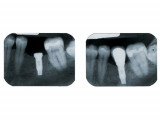

Implants

- Un implant dentaire est une racine artificielle placée par le chirurgien-dentiste dans l'os alvéolaire de l'un des maxillaires en remplacement de la racine d'une dent extraite et servant de support à une prothèse.

Sa forme est généralement cylindrique ou légèrement conique, ressemblant à une vis, en titane ou en zircone, avec une connexion au niveau supérieur, à l'emplacement de la gencive, pour permettre la pose d'un élément prothétique par vissage ou scellement.

Son diamètre varie entre 3 et 5mm et sa longueur entre 8 et 15mm.

Le choix se fait en fonction de l'emplacement, de la quantité d'os disponible, et des éléments anatomiques environnants à partir d'un examen radiologique et scanner de la zone à implanter.

Il faut attendre après la pose de l'implant, l'ostéo-intégration, qui peut durer plusieurs mois. L'implant va se souder complètement avec l'os et contrairement à la dent il n'y a pas de ligament alvéolo-dentaire.